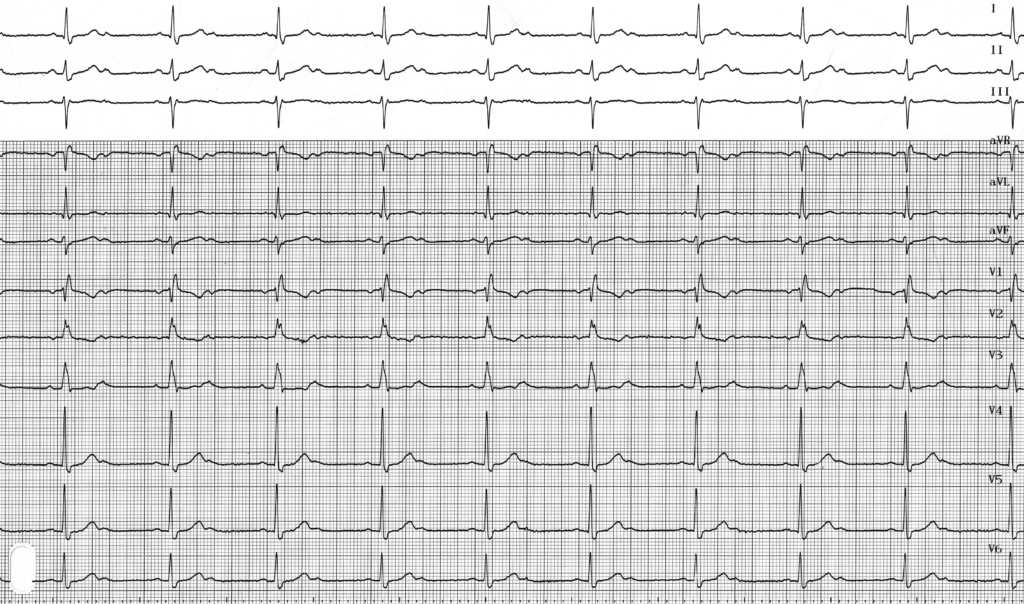

Le BAV 2/1 mérite d’être individualisé parce qu’il est relativement fréquent et qu’il représente la limite entre bloc du second degré et bloc de haut grade puisqu’il comporte autant d’ondes P bloquées que d’ondes P conduites. Il est difficile de déterminer le siège supra-, intra- ou infra-hisien. L’enregistrement de tracés longs peut permettre de révéler un aspect de Luciani-Wenckebach typique avec variations de la durée de l’espace PR (en faveur d’un Mobitz 1 nodal) ou un aspect de Mobitz 2 avec plusieurs ondes P conduites suivies d’une onde P bloquée sans modification de l’espace PR (en faveur d’un bloc intra- ou infra-hisien).

Dans un BAV 2/1, l’intervalle PR des ondes P conduites est habituellement de durée normale mais peut être allongé. On peut observer des variations dans l’espace PP, l’espace PP contenant le QRS étant plus court que l’espace PP sans QRS (arythmie sinusale ventriculo-phasique). Différentes hypothèses ont été proposées pour expliquer cette alternance dans les cycles atriaux (cycle PP court avec QRS, cycle PP long sans QRS): 1) la dépolarisation ventriculaire pourrait favoriser un étirement de l’oreillette droite responsable d’une augmentation de l’automaticité du nœud sinusal et une diminution de l’espace PP; 2) la dépolarisation ventriculaire s’accompagne d’une augmentation du débit cardiaque et d’un effet sur les barorécepteurs s’accompagnant d’une baisse de l’activation parasympathique entrainant une augmentation de la fréquence sinusale;